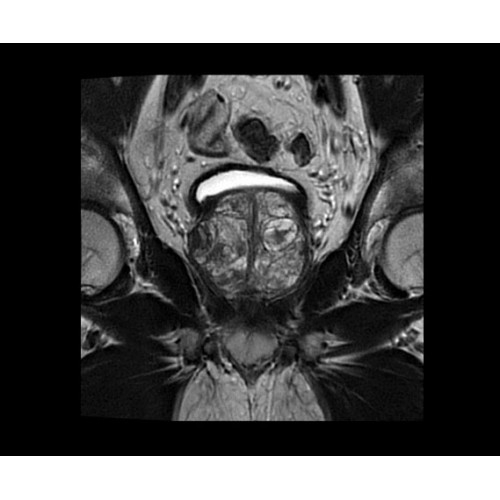

Поле обзора 50x50x50 см и апертура шириной 70 см позволят достоверно визуализировать сложные анатомические области для пациентов с крупным телосложением, например, плечи и бедра. Феноменальная однородность системы SIGNA Architect обеспечивает наиболее широкое поле обзора с улучшенными характеристиками градиентов. Ничто не останется незамеченным.

• BodyWorks — для визуализации абдоминальной и тазовой областей, подстраиваясь под запросы пользователя с учетом любых типов пациентов.